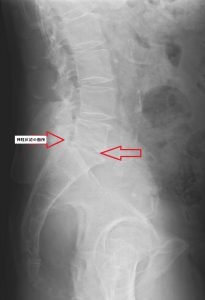

X線検査(レントゲン)では、骨のずれ、腰椎のすべり症などの異常がないか、骨折がないかを調べます。

骨以外にも椎間板が狭くなっていないか、身体の動きによる腰椎の不安定性はないかを確認する必要があります。

X線検査だけでは、診断が困難な脊柱管内での神経の圧迫の状況などはMRI検査をし、その重症度を確認することがあります。